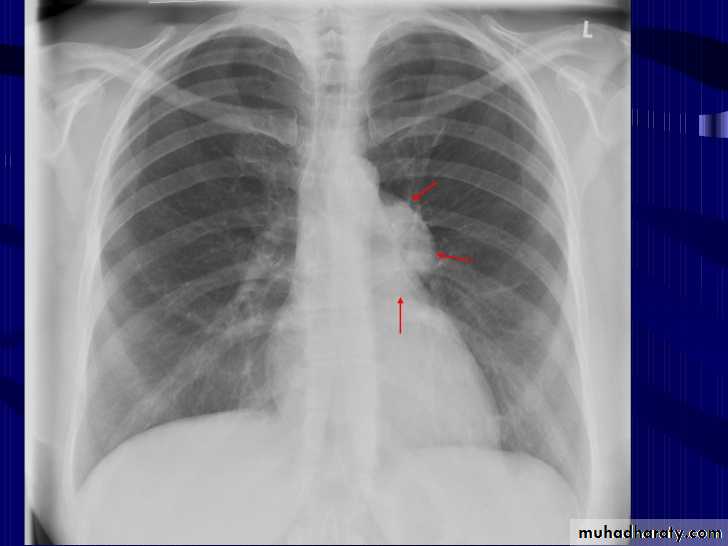

Radiographic featuresPlain film

Typical radiographic features of mitral regurgitation include :

frontal projection

left atrial enlargement

convexity or straightening of the left atrial appendage just below the main pulmonary artery (along left heart border)

double density sign: the right side of the enlarged left atrium pushes into the adjacent lung and creates an addition contour superimposed over the right heart

elevation of the left main bronchus and splaying of the carina

upper zone venous enlargement due to pulmonary venous hypertension

left ventricular enlargement is also eventually present due to volume overload

Features of pulmonary oedema may also be present.